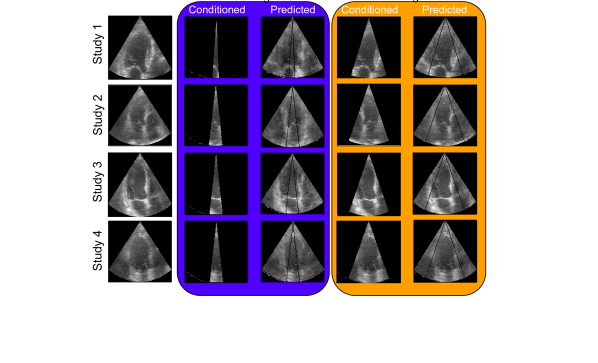

Different size of extended view

We evaluated the influence of the training cone size on the quality of outpainted sections in ultrasound images. Figure 3 illustrate two distinct scenarios: the first utilizes a narrower 10-degree cone cut as the inference input, with the echoGAN algorithm tasked with generating outpainted extensions that span 40 degrees on both sides; the second employs a 60-degree cone cut for inference, with outpainting applied to 15-degree segments on each side. Notably, the generated images appear highly realistic, even when echoGAN is interfaced with only a 10-degree cut. The algorithm demonstrates ability to reproduce cardiac muscle structures with high fidelity. This is particularly evident in the first, second, and fourth rows, where echoGAN successfully outpaints a complete right atrium, that is an encouraging result given that the right atrium was not included in the 10-degree cut, suggesting that echoGAN can reconstruct it entirely. In the case of the left ventricle and left atrium, we observe that echoGAN is capable of outpainting the missing boundary parts for the 30-degree cut and can significantly reconstruct substantial portions of these structures for the 10-degree cut. Again, to quantitavely evaluate the quality of outpainted USG images, we measure FID for different sizes of outpainted regions. The results are provided in Tab. 1. The 30 degree cut means, that echoGAN generates 15 degrees on both sides. Similarly in case of 80 degrees, echoGAN geenrates 40 degree on both sides, using only very narrow 10 degree cone as an input.

As expected, the smaller FID values indicating better similarity are achieved for the cases when the broader cut is used as an input for network inference.

Refer to caption

Figure 3: Extending field of view (yellow) vs basic (teal) for 30 and 80 degree outpainting.